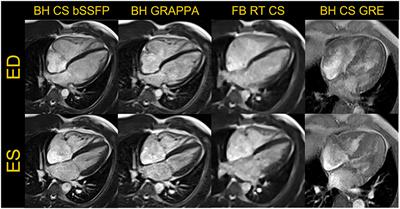

Building a comprehensive cardiovascular magnetic resonance exam on a commercial 0.55 T system: A pictorial essay on potential applications